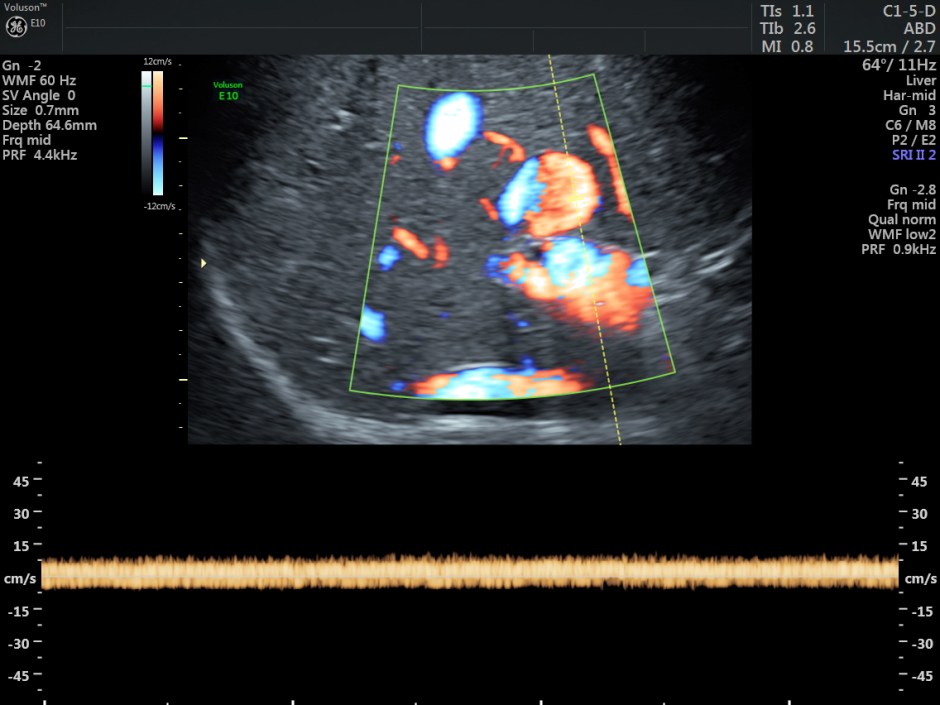

STIC HIGH DEFINITION FLOW reconstruction images also show a feeding vessel and a vessel leaving the vascular structure,

In this patient, the focal saccular dilatation measured 1.71 cms and this could have been a portal venous aneurysm.

No associated findings were made out. The gastroenterologist surgeon advised follow-up after 6 months.